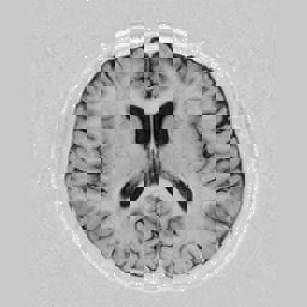

Another larger group of experiments enabled me to study the effects of multi-scale NRR. The results are shown in the form of chequerboard images in Figure [*]. In terms of resolution levels, higher numbers mean that the images are coarser.

Figure: Multi-scale NRR (increasing resolution). From left to right, top then bottom:before NRR; after 5 iterations of NRR at level 2 (higher is coarser); after another 5 iterations of NRR at level 1.